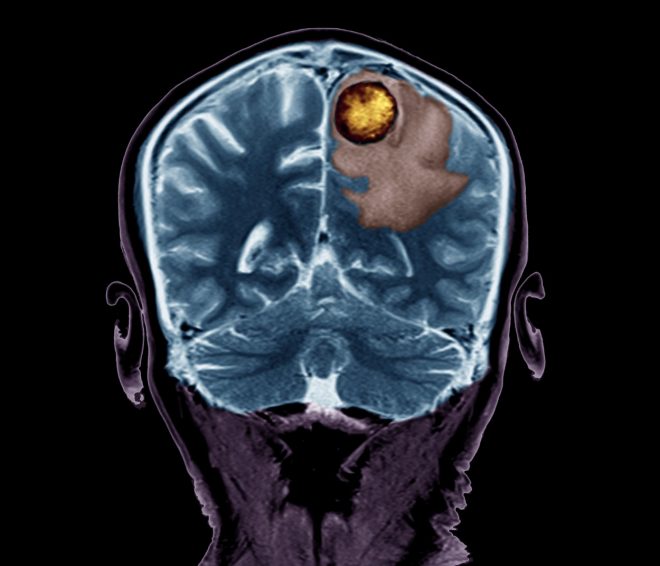

Po napovedih naj bi se obolevnost za rakom do leta 2035 povečala za 24 odstotkov, rak pa naj bi takrat postal vodilni vzrok smrti v Evropski uniji, so zapisali na IJS. Pozitronski emisijski tomografiji, metoda slikanja, ki poda sliko funkcionalnih procesov v telesu, pa je trenutno vodilna tehnika za diagnosticiranje raka. Vendar pa je zaradi visokih stroškov izvedbe na voljo le v manj kot 0,5 odstotkov zdravstvenih centrov na svetu. V projektu PetVision bodo z različnimi tehnološkimi inovacijami ta problem naslovili.

Po besedah IJS bodo raziskovalci v projektu razvili “ultrahiter detektor anihilacijskih žarkov gama in ga uporabili za izdelavo inovativne aparature za funkcionalno medicinsko diagnostiko”. Projekt predvideva tudi “paket prelomnih inovacij v zasnovi detektorja, foto-senzorja in front-end elektronike, ki bi omogočile učinkovitejše diagnosticiranje raka in s tem hitrejše in uspešnejše zdravljenje te bolezni”.

Kot je za STA pojasnil koordinator projekta Rok Pestotnik iz Odseka za eksperimentalno fiziko osnovnih delce IJS, so eden ključnih del pozitronskih tomografov zelo dragi detektorski obroči, ki zaznavajo žarke gama. Nova naprava, ki jo predlagajo raziskovalci, bo imela podobne karakteristike kot detektorski obroč, a bo sestavljena iz dveh manjših panelov. S tem bodo po besedah Pestotnika pocenili celotno aparaturo in jo naredili bolj dostopno zdravstvenemu sistemu in pacientom. Hkrati pa bi metodo lahko uporabili tudi v kakšnih drugih aplikacijah, recimo med samo operacijo, kar doslej ni bilo mogoče, je dejal Pestotnik.